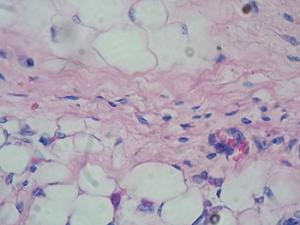

Identifican el papel de la proteína survivina en la expansión patológica del tejido adiposo

Investigadores del <a href="https://www.ciberdem.org/" title="Centro de Investigación Biomédica en Red de Diabetes y Enfermedades Metabólicas Asociadas" alt="Centro de Investigación Biomédica en Red de Diabetes y Enfermedades Metabólicas Asociadas" target="_blank">Centro de Investigación Biomédica en Red de Diabetes y Enfermedades Metabólicas Asociadas</a> (CIBERDEM) y del <a href="http://www.iispv.cat/es_index.html" title="Instituto de Investigación Sanitaria Pere Virgili" alt="Instituto de Investigación Sanitaria Pere Virgili" target="_blank">Instituto de Investigación Sanitaria Pere Virgili</a> (IISPV), liderados por Joan Josep Vendrell y Sonia Fernández-Veledo, acaban de publicar en la revista <a href="https://www.nature.com/articles/cddis2017209a" title="Cell Death &amp; Disease" alt="Cell Death &amp; Disease" target="_blank">Cell Death &amp; Disease</a> un estudio en el que identifican por primera vez el papel de la survivina, una proteína clásicamente relacionada con la progresión del cáncer, en la expansión patológica del tejido adiposo.